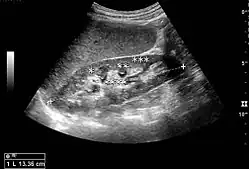

Figure 2. Normal pediatric kidney. * Column of Bertin; ** pyramid; *** cortex; **** sinus.[1] -

The kidney is divided into parenchyma and renal sinus. The renal sinus is hyperechoic and is composed of calyces, the renal pelvis, fat and the major intrarenal vessels. In the normal kidney, the urinary collecting system in the renal sinus is not visible, but it creates a heteroechoic appearance with the interposed fat and vessels. The parenchyma is more hypoechoic and homogenous and is divided into the outermost cortex and the innermost and slightly less echogenic medullary pyramids. Between the pyramids are the cortical infoldings, called columns of Bertin (Figure 1). In the pediatric patient, it is easier to differentiate the hypoechoic medullar pyramids from the more echogenic peripheral zone of the cortex in the parenchyma rim, as well as the columns of Bertin (Figure 2).[1]